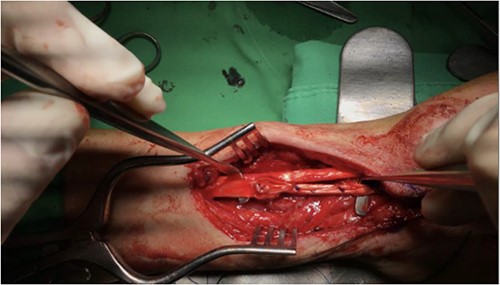

He was admitted to the hospital for further management and underwent plate removal, tenolysis and tendon graft reconstruction on 19 January 2021 (Fig. 2). The operation was successful, and the patient tolerated it well. No post-operative complications were observed. After the surgery, he was prescribed acetaminophen 500 mg four times a day and morphine 5 mg intramuscularly every 4 h as needed for pain control. Wound care with a wound dressing of Biomycin was also prescribed, and his vital signs and wound condition were closely monitored. Infection prevention was done with Cefazolin 1 g intravenously every 8 h.

The patient underwent plate removal, tenolysis and tendon graft reconstruction on 19 January 2021.